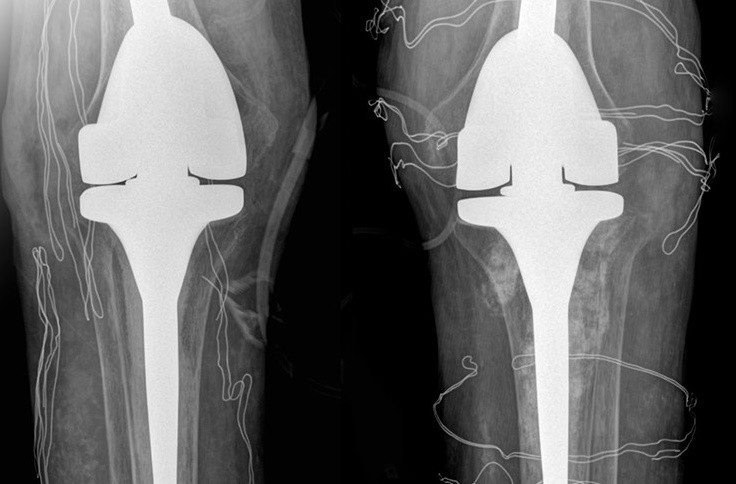

Bác sĩ Quyền phẫu thuật thay hai bên khớp gối cho anh T. Ảnh: Bệnh viện Đa khoa Tâm Anh.

Ê-kíp bác sĩ loại bỏ các hạt tophi gây cản trở vận động, thay thế khớp gối đã tổn thương bằng loại khớp nhân tạo có bản lề, dành riêng cho bệnh nhân có các biến dạng khớp nghiêm trọng. Hậu phẫu, bệnh nhân tiếp tục truyền thuốc ổn định nồng độ hormone tuyến thượng thận trong 2 ngày, sau đó duy trì uống thuốc hormone thay thế.